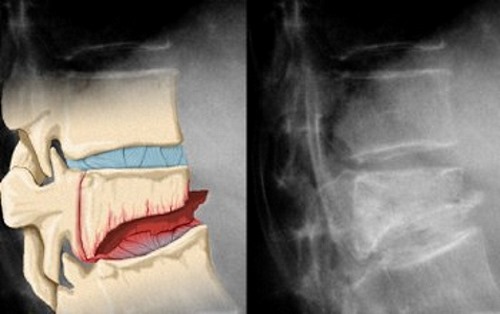

На втором этапе наблюдается разрушение поверхности позвонков, что приводит к выдавливанию ядра и увеличению межпозвоночного пространства. В результате этого формируются протрузии и грыжи межпозвоночных дисков. Эти состояния вызывают интенсивные, постоянные боли, ограничение подвижности, слабость, а также чувство онемения в области лица и рук.

Наибольшую угрозу представляет третья стадия заболевания, которая характеризуется образованием межпозвоночных грыж. В этот период продолжается разрушение поверхности межпозвоночного диска, что увеличивает риск повреждения находящихся рядом кровеносных сосудов, мышц, связок и нервов.

Каждый позвонок становится более острым и грубым, что негативно сказывается на мышцах. В результате непроизвольных сокращений ограничивается подвижность не только шейного отдела, но и всего позвоночника. Это приводит к защемлению нервов, что ухудшает передачу нервных импульсов к различным органам и тканям.